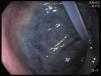

Reportamos el caso de un varón de 44 años de edad, residente de un asilo, bajo alimentación enteral mediante gastrostomía endoscópica percutánea (PEG), desde que sufrió una embolia 2 años antes. De manera accidental se extrajo su sonda de alimentación. Para prevenir el cierre de la gastrostomía, le fue colocado de inmediato una sonda de Foley. Después de varias horas, presentó vómito. Al día siguiente, se llevó a cabo una endoscopia después de haber administrado azul de metileno mediante el catéter. Reveló que la sonda de Foley había atravesado el antro gástrico (fig. 1) con el globo migrando al duodeno (fig. 2) causando obstruccion parcial (fig. 3).

El catéter fue retirado, se introdujo una sonda de PEG, 20F de Bard®, resolviendo así la obstrucción. En casos de extracción accidental de sondas de PEG, con el objeto de evitar que la gastrostomía se cierre, con frecuencia se utilizan sondas de Foley, ya que son fáciles de pasar mediante la gastrostomía y se encuentran disponibles en la mayoría de las instituciones de salud. Sin embargo, no cuentan con un borde externo y la peristalsis podría arrastrar el globo al duodeno originando obstrucción pilórica. En lugar de proceder con la inserción de una sonda de Foley, se debe referir rápidamente a los pacientes a algún centro hospitalario durante las primeras 24h, para poder colocar una sonda de PEG adecuada. Si la remisión temprana resulta imposible, el balón de Foley deberá ser inflado de forma mínima, para prevenir la migración al duodeno y la obstrucción pilórica (figs. 1-3).